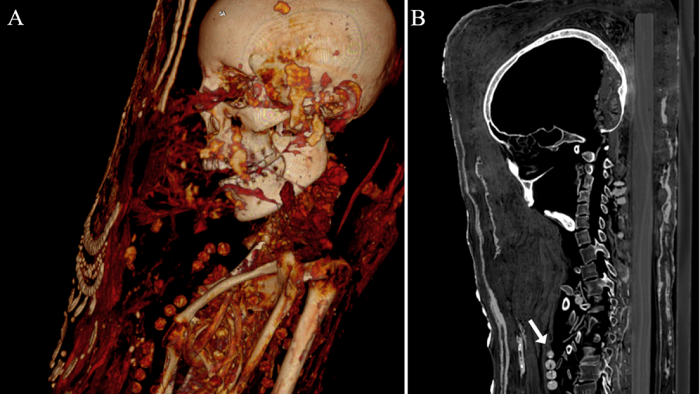

Mediante análisis de tomografía computarizada, los investigadores lograron obtener información sobre el estado de conservación de los cuerpos, la técnica de momificación artificial usada, la edad de los individuos en el momento de la muerte, así como su género, altura y salud.

Las momias, que se corresponden con un hombre adulto, una mujer de mediana edad y otra mujer joven, son las únicas cubiertas de estuco que se han encontrado en la antigua necrópolis de Saqqara. En el proceso, los cuerpos se colocaban sobre tablas de madera antes de se envueltos en tela, yeso y oro, añadiéndose en la superficie un retrato de cuerpo entero.

Además, los expertos identificaron cuentas de collares, una horquilla y objetos de metal denso, como sellos de plomo, clavos y dos monedas o medallones, con los que fueron enterrados los individuos.

Finalmente, los resultados del estudio también revelaron otros datos relacionados con la salud de las tres momias, como la presencia de caries, protuberancias entre las vértebras (nódulos de Schmorl) y evidencia de artritis.